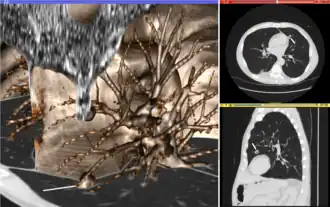

Volume rendering (left), axial cross-section (right top), and sagittal cross-section (right bottom) of a CT image of a subject with multiple nodular lesions (white line) in the lung

Visualization plays several key roles in medical image computing. Methods from scientific visualization are used to understand and communicate about medical images, which are inherently spatial-temporal. Data visualization and data analysis are used on unstructured data forms, for example when evaluating statistical measures derived during algorithmic processing. Direct interaction with data, a key feature of the visualization process, is used to perform visual queries about data, annotate images, guide segmentation and registration processes, and control the visual representation of data (by controlling lighting rendering properties and viewing parameters). Visualization is used both for initial exploration and for conveying intermediate and final results of analyses.

The figure "Visualization of Medical Imaging" illustrates several types of visualization: 1. the display of cross-sections as gray scale images; 2. reformatted views of gray scale images (the sagittal view in this example has a different orientation than the original direction of the image acquisition; and 3. A 3D volume rendering of the same data. The nodular lesion is clearly visible in the different presentations and has been annotated with a white line.